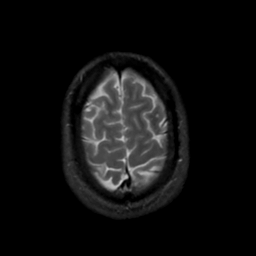

MR Study #7, March 24, 1991 -- Slice #43

[Home][Help][Clinical][Tour 1][Tour 2] Slice 43